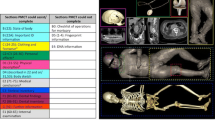

Details of each scan are presented in Online Resource 2 with the pig tissue, archaeological specimens, and other items scanned in pre-set groupings. For the first scanning session, pigs’ trotters wrapped in cling film, simulated wet bone scenarios and were commingled with the bullets, casings, natural debris, and personal effects inside a body bag. The same was done with the archaeological and anatomical human remains that represented dry bone scenarios. A pig’s trotter was charred in a fast-burning fire for 15 min before being scanned, and archaeological cremated bone samples were scanned to explore whether or not cremated bone could be identified. Animal and human bones, as well as commingled human bones, were grouped together as the human vs non-human bone identification is often the first question forensic anthropologists have to answer (Fig. 1). Bones showing ante-mortem trauma were scanned to see if the healed fractures could be observed, and bones evidencing pathological conditions (e.g. degenerative joint disease on vertebral bodies) were also scanned for their ability to be seen. The body bags were placed on a wooden tray to help avoid unnecessary movement of the bag as it passed through the curtains at the tunnel entrance, as this would result in a stretched and distorted image.

An articulated wired skeleton (torso) dressed in a shirt with personal effects placed in the pockets (Fig. 5a) showed good detail of the spine and ribs without any interference from the clothing and personal effects, allowing examination of these bones for any trauma or identifying features (Fig. 5b). In this image, the clothing was presented as a very faint orange and could barely be seen and the bullets and casings again appeared as dark and light blue respectively. In Fig. 6, ante-mortem trauma (healed fractures) can be observed on both fibulae. For those bones exhibiting pathological alteration, the lesions on the bone were also visible to a certain degree in the images. Juvenile bones were imaged as well, and the growth plates were visible as a darker green compared with the rest of the bone. The incompleteness of the shape of the bones was also evident (Fig. 7). In a scan of commingled human remains, bones from more than one individual were identified and a scan of human and animal bones showed clear differences in size and shape.

Photograph of clothed, articulated torso with personal effects in the pockets (top), scanner image of the articulated torso with clothing and personal effects visible (bottom). The torso bones were articulated using a metal rod, wire, and screws which are visible in the scanner image. The clothing is barely seen, allowing the observer to immediately see the bones and personal effects, including hazardous items such as bullets